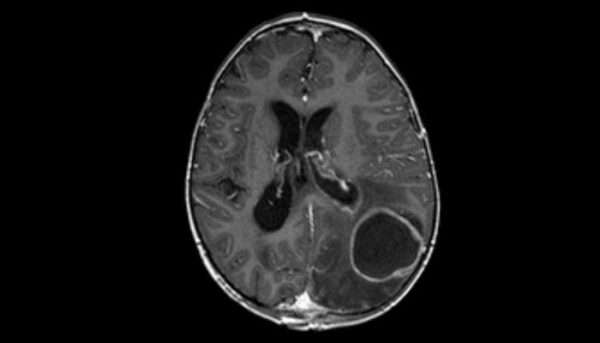

La tomografía computarizada de la cabeza en pacientes con absceso cerebral revela características radiológicas distintivas que ayudan en el diagnóstico de esta afección. Una de las principales características es la presencia de un área de realce con contraste que rodea un núcleo de baja densidad. Este patrón se debe a la localización de la infección, donde el absceso presenta una cápsula externa que se realza con el contraste debido a la vasodilatación y la inflamación en la zona periférica del absceso, mientras que el centro del absceso, compuesto principalmente de material purulento, tiene una densidad baja debido a la falta de estructuras celulares densas y la presencia de líquido infectado. Esta imagen es bastante característica de un absceso cerebral y, aunque puede observarse también en otras patologías, como los neoplasmas metastásicos, la combinación del realce periférico con un núcleo central de baja densidad es más típica de un absceso.

A pesar de que la tomografía computarizada es útil para la visualización del absceso, la resonancia magnética (RM) tiene ventajas adicionales. En particular, la RM permite la detección temprana de cambios en el cerebro que pueden ser indicativos de cerebritis focal o de un absceso en fases más iniciales, antes de que el absceso esté completamente formado. La resonancia magnética es especialmente valiosa debido a su mayor resolución espacial y su capacidad para diferenciar de manera más precisa entre los diferentes tipos de tejidos cerebrales y las lesiones, lo que permite identificar con mayor claridad las características patológicas del absceso, como el edema circundante y la inflamación en las áreas adyacentes al absceso. Además, la RM con secuencias ponderadas por difusión puede ofrecer información adicional sobre la extensión de la infección en los tejidos cerebrales circundantes y la presencia de cambios inflamatorios sutiles, que pueden no ser tan evidentes en una TC.